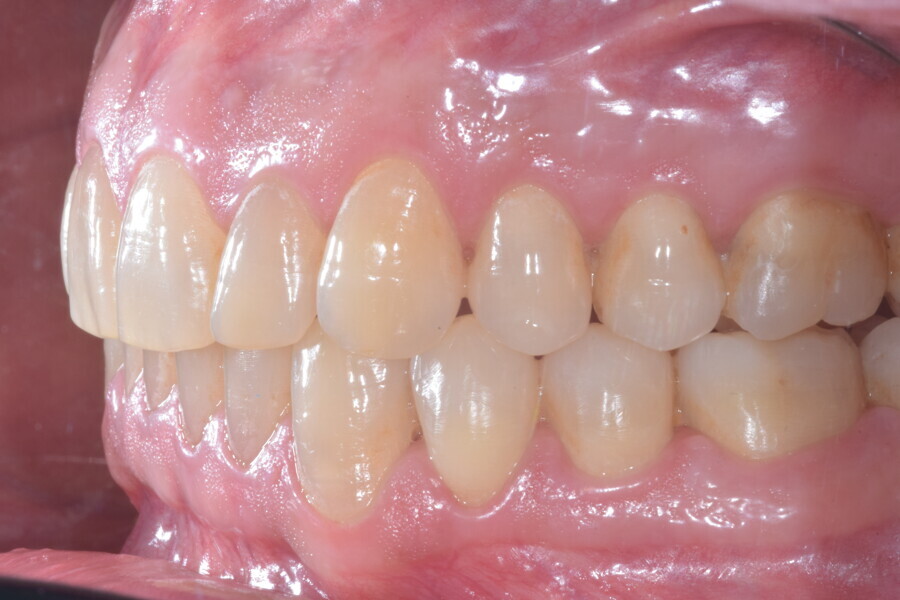

A 37-year-old male patient presented with the chief need for re establishing anterior alignment in both arches. Facial analysis showed a short face with a flat profile but proper chin projection (Figs. 9–12), and clinical examination revealed a skeletal Class I (ANB = 0.89°) and dental Class I malocclusion with severe deep bite (almost 100%), a deep curve of Spee, normal maxillary central incisor torque (Ui–FH = 110°), mild maxillary crowding and moderate mandibular crowding (Figs. 13–18). The deep bite components were represented in this patient by the severe skeletal condition of hypo divergent pattern (FMA = 14.24°) with normal maxillary and mandibular incisor inclination and decreased gonial angle (110.46°). Analysis of the cephalometric radiograph indicated a reduced lower anterior facial height, combined with a hypo-divergent pattern (Fig. 19). The only treatment option suggested was orthodontic treatment with aligners for deep bite correction with all the features described (bite ramps, pressure area, 3D curve of Spee levelling, Class II elastics and heavy occlusal contacts).

The digital treatment plan (ClinCheck) provided 12 aligners for the maxillary arch and 17 for the mandibular arch. The treatment objectives were focused on coupled vertical movements of posterior extrusion and anterior intrusion by means of bite ramps, providing for posterior disocclusion and anterior intrusion of mandibular teeth by means of extrusion attachments needed for mandibular arch levelling. The maxillary and mandibular incisors were proclined to level the upper and lower curve of Spee and to support the flat profile and the lips. Class II elastics were planned to support mandibular proclination and heavy posterior occlusal contacts with relative posterior extrusion. Lateral and posterior maxillary torque were planned to be close to 0°, to achieve wider arch design and ideal intercuspation. No digital over-engineering was planned in the set-up. Because of the age of the patient, the aligners were changed every ten days for a treatment time of less than six months. At the end of the first stage of aligners (Figs. 20–24), an additional stage was planned to improve molar intercuspation without elastics with a digital plan of five further aligners. This brought the total treatment time to 7.5 months since the additional aligners were changed every week.

At the end of the treatment, Class I canine and molar relationships were obtained, maxillary incisor inclination was slightly increased (Ui–FH = 112°), mandibular incisor inclination (IMPA = 97.09°) was fully corrected by means of proclination and the divergency was slightly increased (SN–GoGn = 27°) because of the relative posterior extrusion and use of Class II elastics—a small variation (1°), which is interesting considering the age of the patient (Figs. 25–35). A balanced smile arc was obtained with an ideal relationship between the maxillary incisors and lower lip, and torque control of the lateral and posterior segments generated a broader smile.